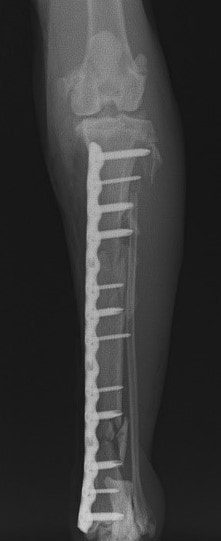

脛骨骨折 : 症例1 | 症例2 | 症例3 | 症例4 | 症例5

当院ではAdvanced Locking plate system(ALPS)と、Locking compression plate system(LCPS)という骨接合法で骨折症例の治療を行っています。

LCPは、スクリュー(ネジ)とプレート(金属の板)をロックする特殊な構造により骨折部位を固定する新しい世代のプレートシステムです。ひとつのホールでロッキングスクリューとスタンダードスクリューの使用を選択できるユニークな構造をしているため、骨折断端間の圧迫を目的とした従来型プレート固定法に加え、高い角度安定性を有するロッキングスクリューを用いた固定法の選択が可能です。従来のプレートシステムでは困難だった部分の骨折や癒合不全の症例に高い治療効果をもたらします。